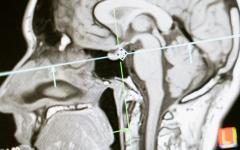

COVID-19 и неврологични заболявания

По време на хоспитализация на пациенти с COVID-19 може да се проявят тежки неврологични усложнения, като гърчове, енцефалопатия, енцефалит, мозъчносъдови инциденти и др.